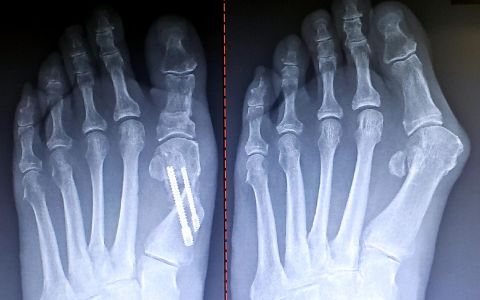

RE: Re-evaluation of Traditional Angular Parameters for Austin Bunionectomies

I have also had success with the minimally invasive Chevron Akin osteotomy (MICA). The technology of the chamfered screw has dramatically changed my pre-operative considerations/parameters. I agree that piercing the far lateral cortex with the chamfered screw provides the stable construct for the correction.

Post and pre-op x-rays |

I also believe that healing of this aggressive correction can be attributed to minimal disruption of the periosteum, soft tissues, and joint capsule. As with other types of MIS bunionectomies currently being performed, joint range of motion is essentially unaffected because the osteotomies are extra-capsular. The case (above) presented is approximately 10 weeks post-operative.

Disclosure: I am a paid consultant for Wright Medical.

Eric Baskin, DPM, Manahawkin, NJ